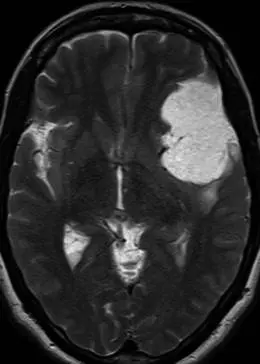

一名有8年暈厥發(fā)作史的55歲女性的軸向T2加權(quán)序列顯示

一名有8年暈厥發(fā)作史的55歲女性的軸向T2加權(quán)序列顯示,左額葉下外側(cè)和前顳葉有一個(gè)巨大的軸外腫塊,明顯高信號(hào),略高于腦嵴液。腫塊后方有輕度血管源性水腫。組織學(xué)符合微囊性腦膜瘤。